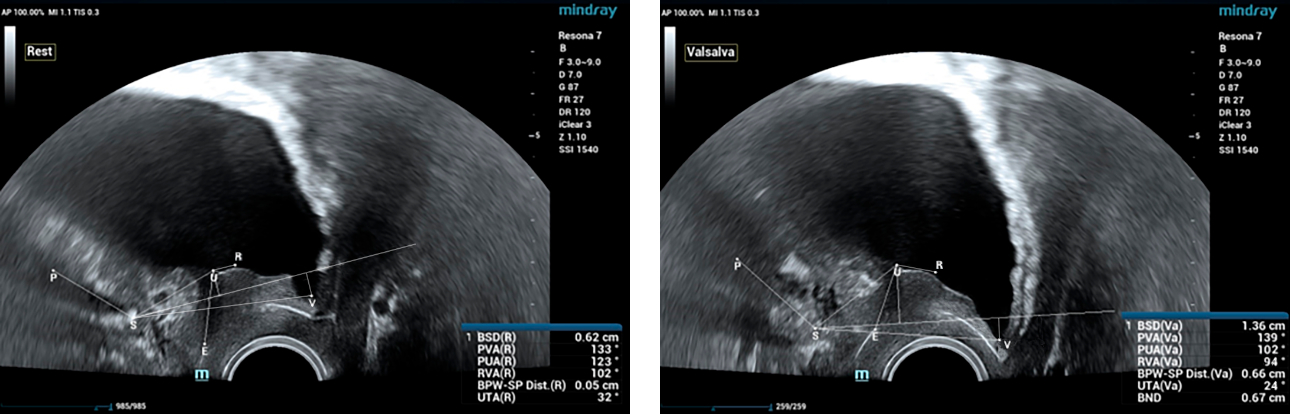

??????? ??? ?? ? ??? ??? ??? ?????, ?? ??(pelvic floor) ??? ??? ?? ??(??? ?/?? ??)? ??? ???. ? ?? ???? PVA, RVA ? PUA ?? 20┬░ ???? ?????. ? ?? ???? PVA ŌĆō 134o, RVA ŌĆō 82o ? PUA ŌĆō 119o.

??? ???? ??? ?? ????? ??? ??? ?? ?????. ????? ? ??? 30mm?? 42mm?? ??? ? ??? ??? ??? ????? ?? ? ? ?? ? ?? ? ?? ??? ??? ??? ? ????. ?? R ? ???? ?? ?? ?? ?? ?? 7mm, ?? ?? 8mm???.